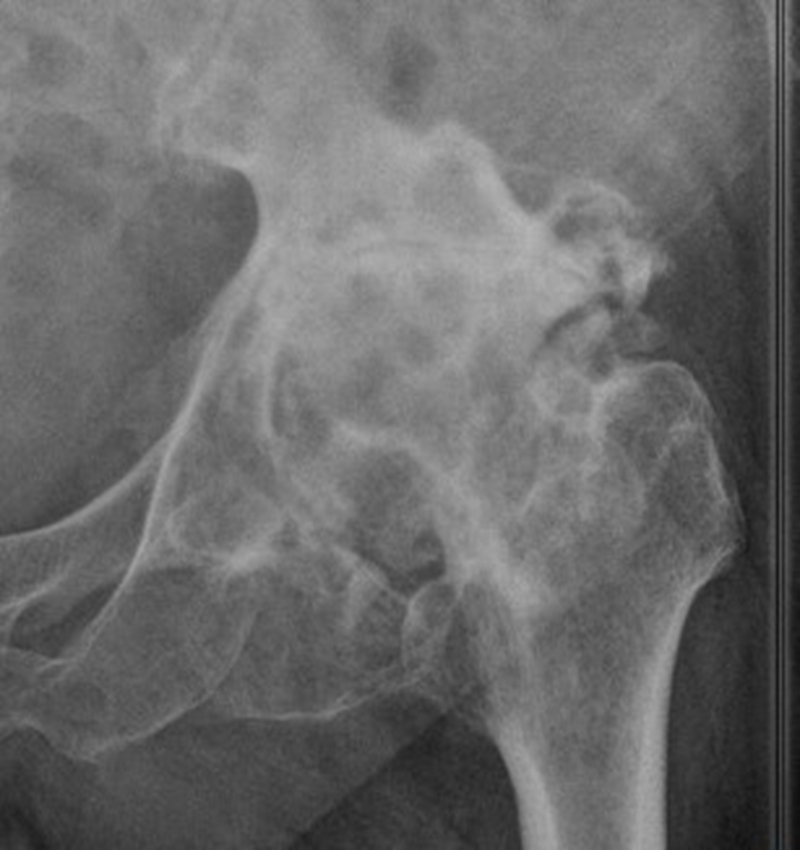

Ⅲ、干骺端畸形

硬化骨、骨赘、骨质疏松、髓腔宽大

转子间骨折畸形愈合后常导致干骺端畸形,干骺端遗留大量硬化骨或髓腔成角,术中需在确认髓腔开口位置后,首选用小骨刀或高速磨钻去除硬化骨,打通髓腔。

干骺端畸形还可引起髓腔增宽,骨量减少,骨质疏松,不能为近端压配固定型的假体提供良好稳定。宜选用全微孔涂层远端固定假体。